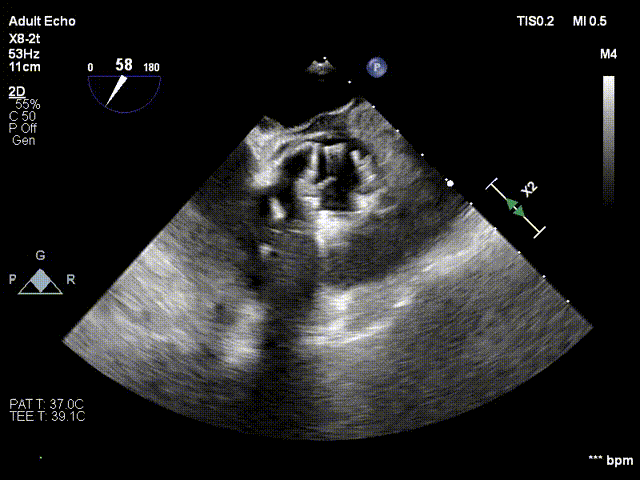

术前、术后超声对比

术后

术后超声显示瓣口未见明显反流,无瓣周漏,主动脉瓣前向血流加速Vmax=1.65m/s,有效开口面积1.61cm²,PGmean=4mmHg。术后监测,心率心电正常,无传导阻滞。患者生命体征稳定。本次手术植入瓣膜定位准确,操作简便,症状即刻改善,手术圆满成功。